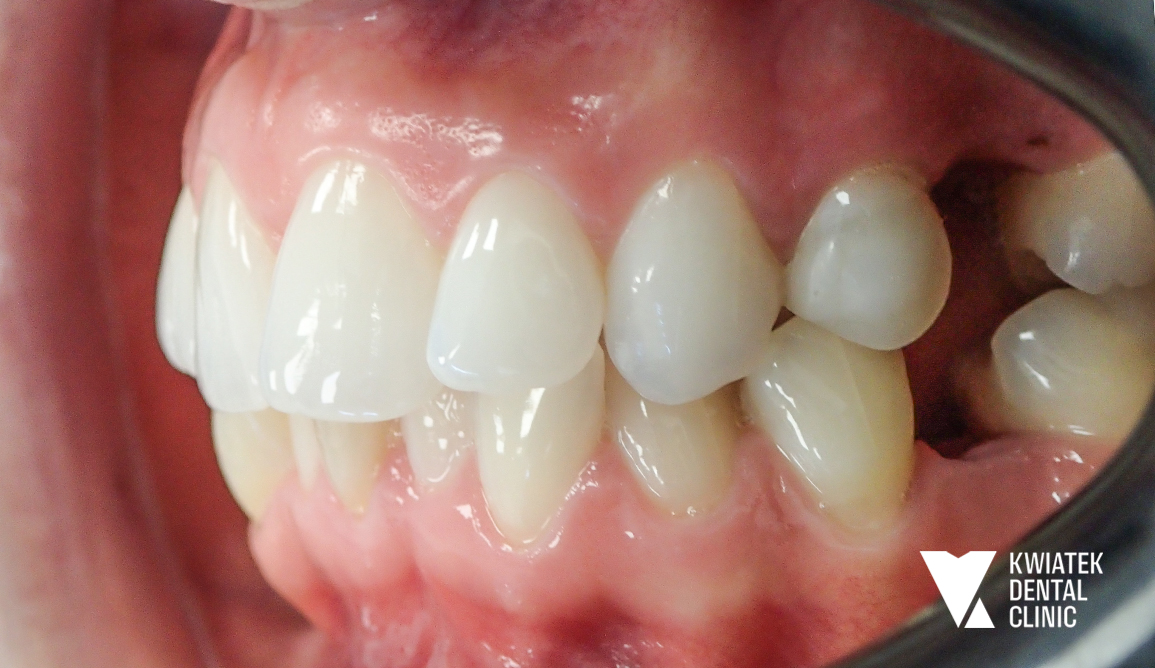

PRZED

Historia tej metamorfozy pokazuje, jak ogromne znaczenie ma kompleksowe podejście do leczenia stomatologicznego. Pacjentka zgłosiła się z chęcią poprawy estetyki uśmiechu, jednak już pierwsza konsultacja ujawniła, że kluczem do osiągnięcia trwałego efektu będzie nie tylko estetyka, ale przede wszystkim przywrócenie zdrowia i prawidłowej funkcji całego układu stomatognatycznego. To właśnie takie przypadki wymagają indywidualnego planu leczenia, cierpliwości oraz ścisłej współpracy Pacjentki z zespołem specjalistów.

Szczegółowa diagnostyka, obejmująca badanie kliniczne oraz zdjęcie panoramiczne, wykazała rozległe potrzeby lecznicze. Zidentyfikowano:

• liczne ubytki próchnicowe oraz nieszczelne wypełnienia

• konieczność leczenia kanałowego zębów 24 oraz 41

• obecność zębów zatrzymanych i korzeni wymagających ekstrakcji

• znaczne nagromadzenie kamienia nazębnego oraz niedostateczną higienę

• wyraźne stłoczenia zębów, szczególnie w łuku dolnym

• zaburzenia zgryzu oraz brak miejsca na odbudowy implantologiczne

Diagnostyka ortodontyczna potwierdziła dodatkowo przesunięcie linii pośrodkowej oraz niewystarczającą przestrzeń w łukach zębowych, co wymagało precyzyjnego planowania leczenia.